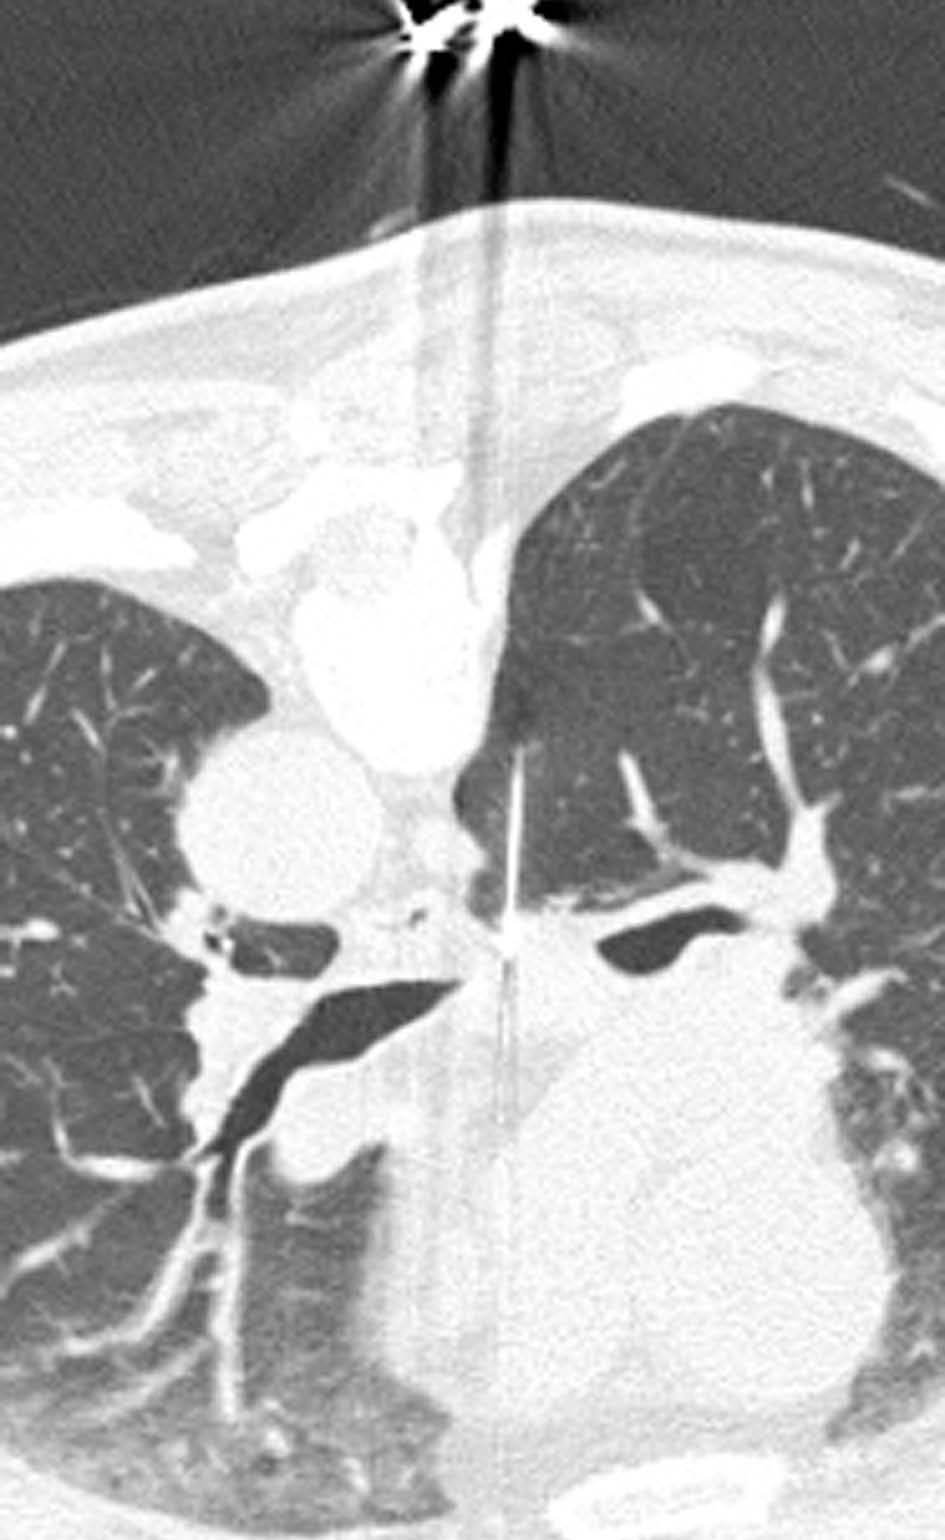

Valoración del tumor

El estadio tumoral (T) se basa en el tamaño, localización y relación con las estructuras adyacentes valorado mediante TC. Los tumores T1 son aquellos de 3 cm o menores en su diámetro mayor, rodeados de pulmón y que no invaden la pleura visceral ni los bronquios principales, mientras que los T2 son lesiones mayores de 3 cm, o aquellas que invaden la pleura visceral o al bronquio principal a más de 2 cm de la carina o que condicionan atelectasia o neumonitis obstructiva que no afecte a todo el pulmón. La diferenciación entre ambos estadios tumorales suele ser sencilla mediante TC, salvo la afectación de la pleura visceral, aunque esta no tiene un impacto importante en el manejo clínico. El tumor T3 viene determinado por la infiltración de estructuras vecinas potencialmente resecables, como la pared torácica, diafragma, pleura mediastínica, pericardio parietal o si el tumor está situado a menos de 2 cm de la carina (fig. 1). Los tumores T4 son aquellos que no pueden ser resecados porque engloban a estructuras vitales, invaden el corazón, grandes vasos, esófago o cuerpos vertebrales (fig. 2) o en los que existe un nódulo o nódulos en el mismo lóbulo del tumor. Además de definir la T, es importante reflejar las particularidades de la infiltración de estructuras en vecindad que puedan modificar la actitud terapéutica. Por ejemplo, cambiará la estrategia quirúrgica según el tipo de bronquio afecto o la estructura mediastínica infiltrada, si es sólo la grasa, o un vaso; cuando existe neumonitis o atelectasia secundaria a un tumor central, la planificación del campo de radioterapia dependerá del límite entre la masa y la repercusión pulmonar.

Fig. 1.--T3. (A) Reconstrucción multiplanar (MPR) de tomografía computarizada (TC) torácica con contraste con ventana de pulmón. Atelectasia completa del lóbulo inferior derecho secundario a tumor endobronquial situado a menos de 2 cm de la carina (flecha hueca). (B) La misma reconstrucción con ventana de mediastino muestra el tumor (flechas) diferenciado de la atelectasia (asterisco). Derrame pleural (DP).

La diferenciación entre tumores T3 y T4 puede ser difícil empleando sólo técnicas de imagen. Cuando se evidencia destrucción ósea (costal o vertebral), existe masa en el espacio intercostal (fig. 3), o las estructuras mediastínicas están claramente englobadas por el tumor, el diagnóstico es obvio (fig. 2). Sin embargo, sin estos hallazgos, la predicción de invasión es mucho menos fiable. Se han descrito diferentes signos que pueden ayudar a determinar la invasión de pared torácica. Éstos incluyen el contacto con la superficie pleural mayor de 3 cm, el engrosamiento pleural, la ausencia de plano graso y la presencia de un ángulo obtuso entre el tumor y la pared torácica. Aplicando al menos dos de estos criterios la sensibilidad es de un 87%, sin embargo la especificidad es baja (59%)4. El dolor torácico localizado es un síntoma importante que a menudo está asociado a invasión de pared.